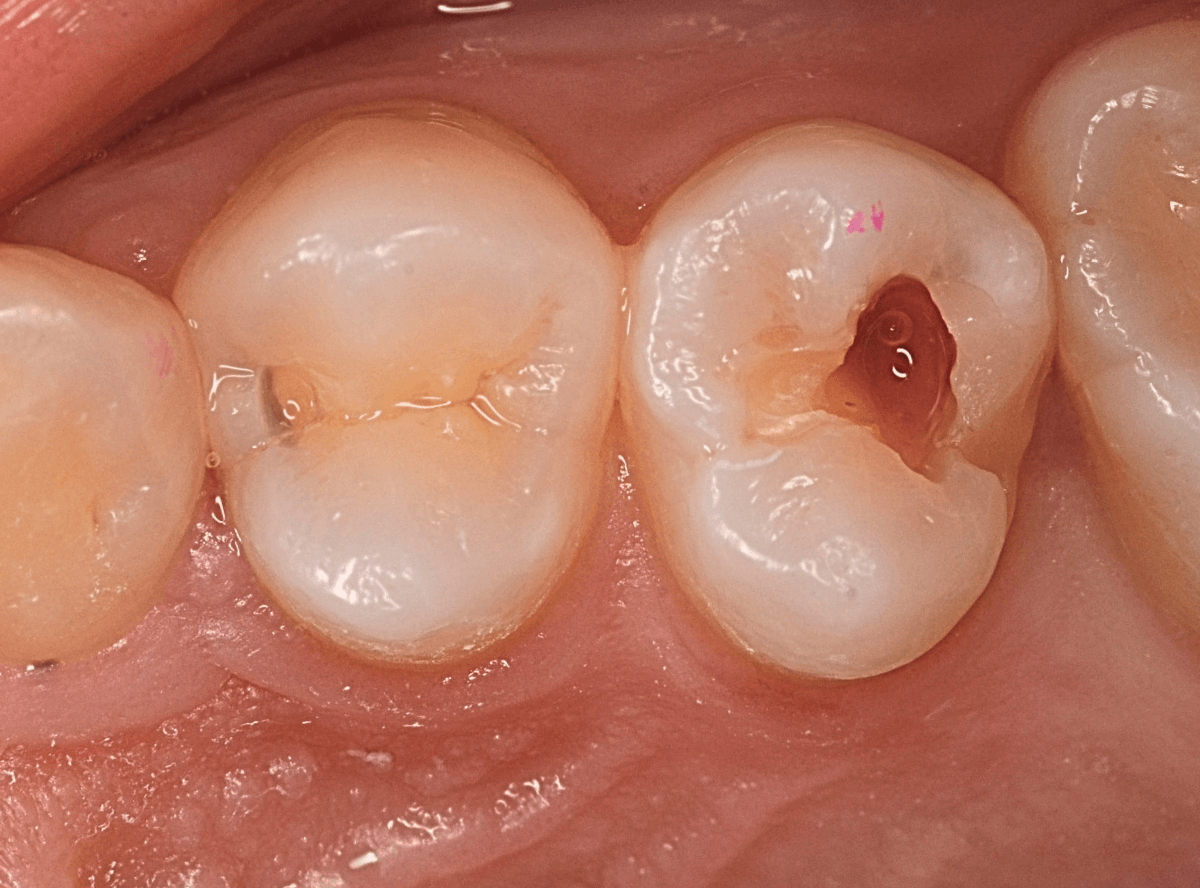

虫歯の治療希望で来院された患者さんです。

レジンが欠けて大きな穴が空いているのが見えます。

このような場合は、中で虫歯が進行している事が多いです。

(レジンの中で虫歯が進行してレジンに穴が空いた、レジンが欠けたのを放置して虫歯が進行したパターンなどがあります)

レントゲン写真で確認します。

青い線が歯の神経です。

赤い線が虫歯と思われる部分です。

思った通り、神経に達してしまいそうな大きな虫歯です。

患者さんには、神経を取る治療が必要な可能性が高い事を説明します。

治療開始です。

まず、慎重にレジンを除去します。

レジンの中の虫歯治療で難しいのは、レジンが歯と同じ色をしているために、歯なのかレジンなのか見分けがつきにくい時がある事です。

この写真でも、レジンがまだ残っているのがわかるでしょうか?

白い〇の部分です。

レジンを全て除去しないと、その下の虫歯を取り残してしまいます。

う蝕検知液で、虫歯の部分を判別しても、レジンが残っていると、わかりづらいです。

慎重にレジンを除去すると、歯の神経が顔を出してきました(露髄)。

レジンを除去したところでもう一度染め出しをしてみます。

神経の周りも虫歯で真っ赤に染まります。

露髄した部分が広がらないように、慎重に虫歯を除去しました。

幸い、それ以上広がる事はありませんでしたので、なんとか神経が残せる可能性が高いです。

お薬とセメントをつめて、経過観察します。

痛みが出ませんように・・・。